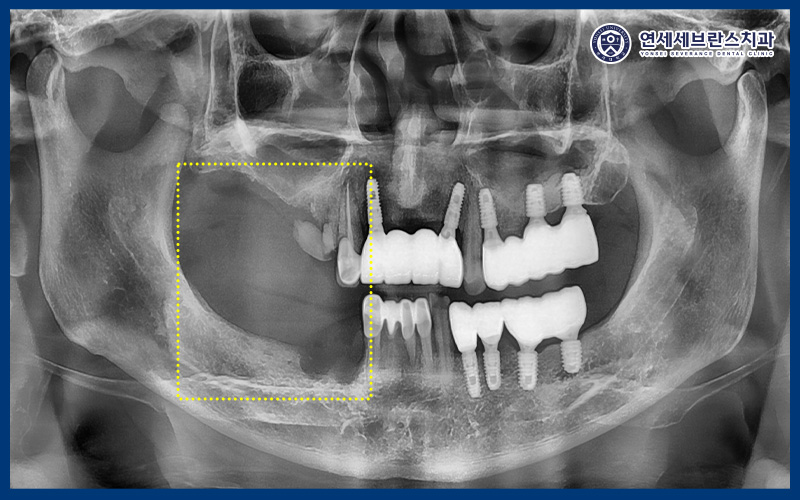

파노라마 사진을 촬영하여

확인해 본 결과,

오른쪽 치아는 대부분

이미 발치된 상태였으며

남아 있던 송곳니 역시 치근 우식과

심한 동요도가 관찰되었습니다.

또한 송곳니 옆 치아는

뿌리만 남아 있는것으로

확인되었습니다.

이러한 치아들은 보존하여 사용하기에는

예후가 좋지 않다고 판단되어,

곡반정동치과 연세세브란스치과수원에서는

발치를 진행한 뒤 뼈이식을 동반한

임플란트 식립을 계획하였습니다.

아울러 위쪽 큰 어금니 부위는

잇몸뼈의 두께가 얇아 임플란트를

바로 식립하기 어려운 상태였기 때문에,

상악동거상술을 시행하여

충분한 뼈이식을 진행한 후

임플란트를 식립하기로 하였습니다.

또한 아래쪽에서 자연적으로

치아가 빠진 부위의 경우,

약 한 달 정도 자연 치유 기간을 가진 뒤

뼈이식을 동반하여 임플란트를

식립하는 치료 계획을 수립하였습니다.